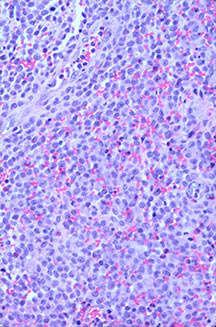

Microscopic Pathology

- Langerhans cell is diagnostic and clonal proliferation

- Nuclei show prominent nuclear groove (coffee-bean)

- Also composed of eosinophils and other inflammatory cells (non diagnostic component)

- Ratio of inflammatory cells to Langerhans cells varies

- Eosinophils dominate some areas forming diffuse sheets, excluding Langerhans cells